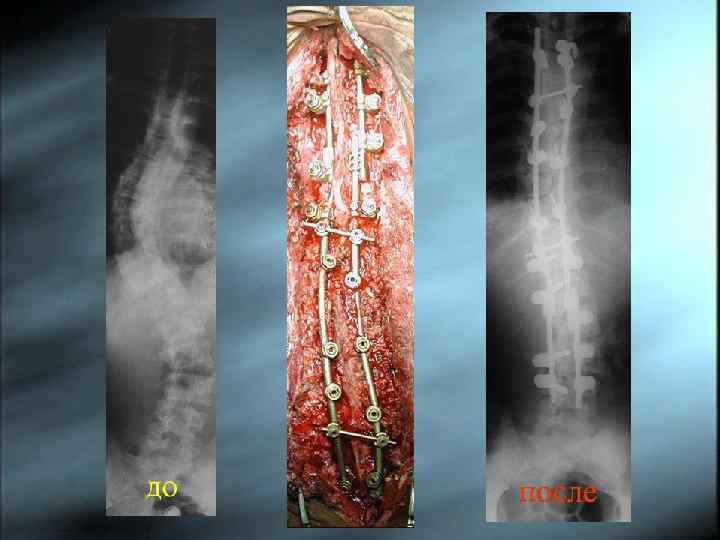

Оперативное лечение Оперативное лечение